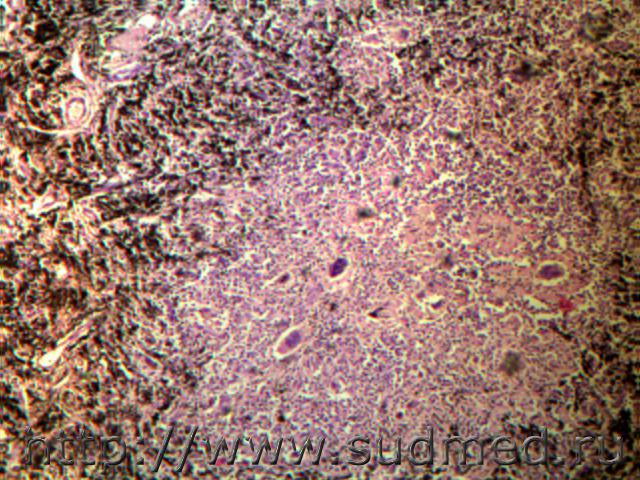

тоже самоповешение двухмесячной давности

меланома, метастазы в сердце и почках